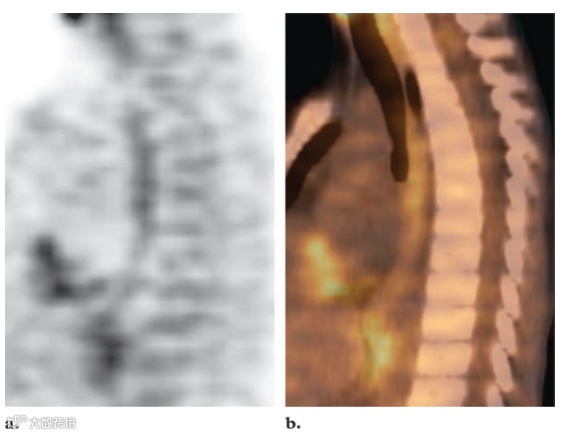

正常胃肠道对FDG的摄取变异很大,范围从轻微到强烈,呈局灶性、弥漫性或节段性分布。胃肠道对FDG摄取的原理尚不完全清楚,可能由多种因素引起。它可能与活跃的平滑肌、活跃的粘膜、吞咽的分泌物或微生物摄取有关。食管摄取可以注意到脊柱前部有轻微的线性摄取,在矢状面上看得最清楚(图8)。患有反流性食管炎或放射治疗后食管炎的患者,食管沿线会出现明显的摄取。患有食管裂孔疝和巴雷特食管的患者,远端食管的摄取也可能增加。通常可发现与胃壁相对应的曲线均匀摄取(图9)。如果胃部收缩,则可以看到一个圆形的中等活动区域。胃部摄取通常较轻,但更强烈的摄取可能与幽门螺杆菌感染有关。

图8. 矢状FDG PET 扫描 (a) 和融合PET/CT图像 (b) 显示胸椎前部线性18F FDG 摄取 (a),此发现与正常食管 (b) 相对应。